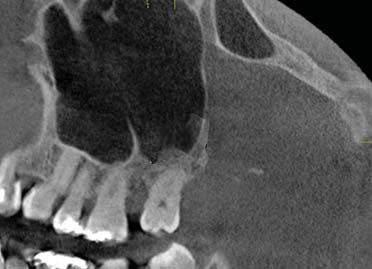

Los septos secundarios, tienen un origen adquirido asociado a atrofia del hueso maxilar como consecuencia de pérdida de dientes, siendo más frecuentes en el piso del seno. La longitud de éstos septos suele ser inferior que los primarios (2,7,12,15,16,17,18). (figura 4 y 5). Gonzales et al., consideraron septos primarios a aquellos donde hay piezas dentarias presentes y los septos secundarios en zonas edéntulas (6).

Rosano et al., Maestre et al., y Van Zyl et al., indicaron que los septos primarios se forman debido al desarrollo radicular, producto de ello habrán separaciones intermedias del piso antral, dando lugar a la localización de los tabiques entre raíces dentarias, este concepto justificaría su predominio en esta población (7,13,18).